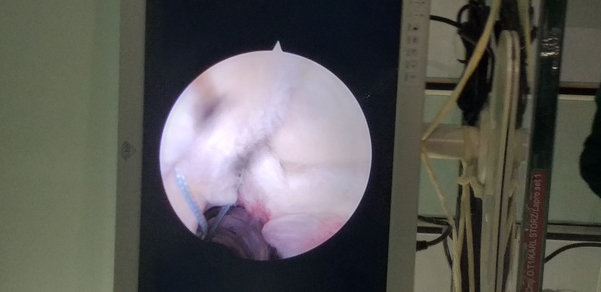

SLAP Tear Repair. Arthroscopic Reconstruction